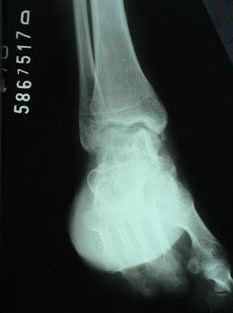

Hálux Rígido

O hálux rígido é uma patologia que afeta a articulação metatarsofalangeana do hálux, promovendo uma alteração degenerativa que leva à perda progressiva da mobilidade articular. Sua etiologia ainda não está totalmente definida, porém, pode estar relacionada a episódios de trauma, mas também pode estar associada a um primeiro metatarso elevado (verticalizado).

Os principais sinais e sintomas clínicos são dores na articulação metatarsofalangeana, perda progressiva da mobilidade e incapacidade ou dificuldade para usar salto, além de uma saliência dorsal. Existem vários níveis de gravidade, e o tratamento se baseia no aspecto clínico e radiográfico. Além disso, indicamos o tratamento conservador nos casos mais leves e em indivíduos com pouca perda da qualidade de vida. O tratamento cirúrgico pode variar de uma queilectomia (limpeza articular) aberta ou artroscópica as cirurgias mais complexas como osteotomias e artrodese (fusão articular).